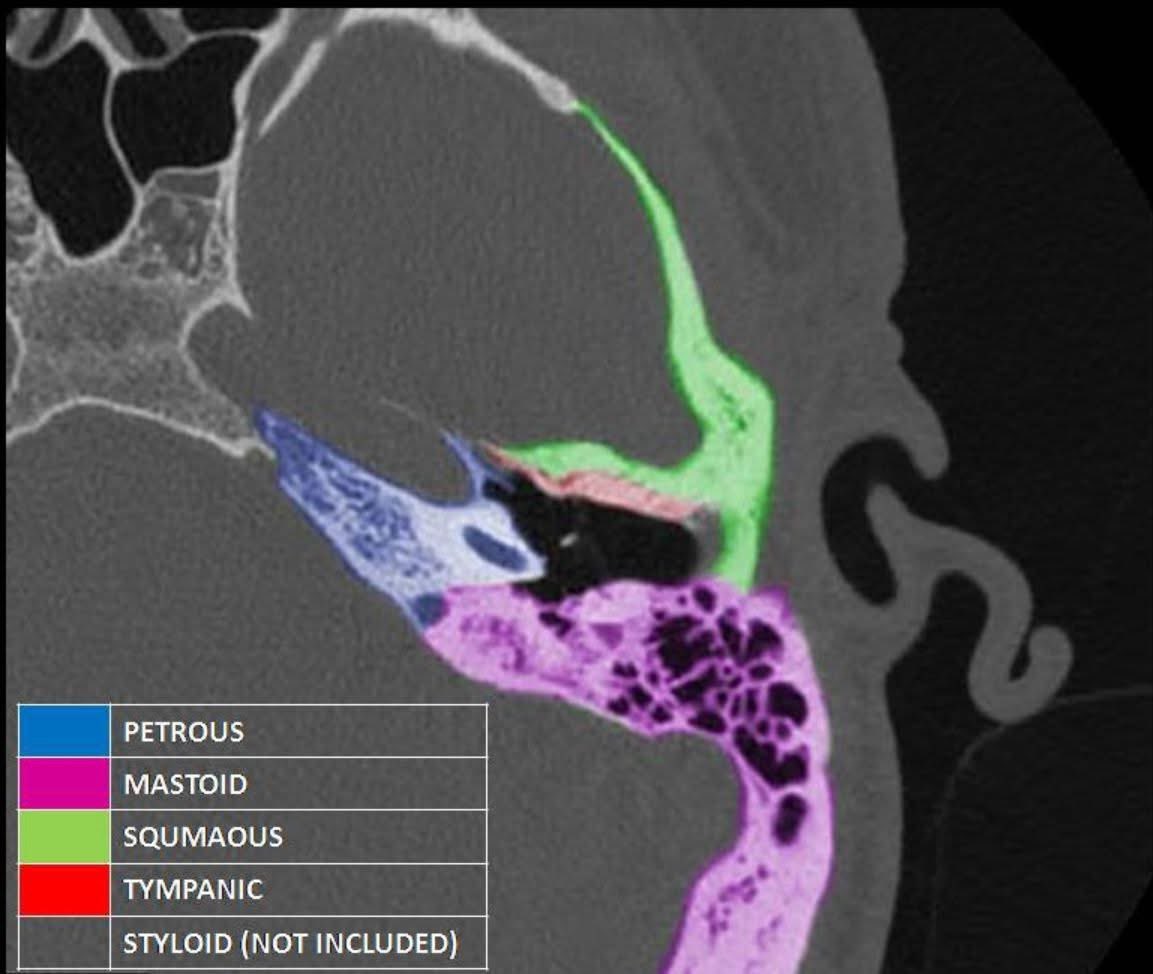

Temporal Bone. CT scan.